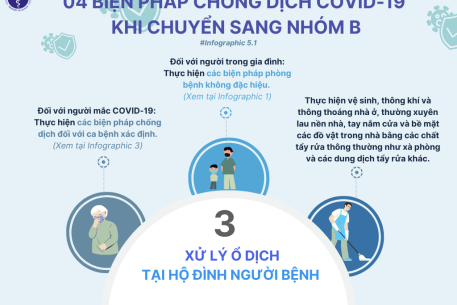

Bộ Y tế thông tin nhanh về các trường hợp mắc bệnh chưa rõ nguyên nhân tại Liên bang Nga

Những ngày gần đây, hệ thống giám sát dựa vào sự kiện ghi nhận thông tin từ các kênh truyền thông báo chí và mạng xã hội về các trường hợp mắc bệnh không rõ nguyên nhân trên người tại Liên bang Nga; Cục Phòng bệnh, Bộ Y tế thông tin như sau: